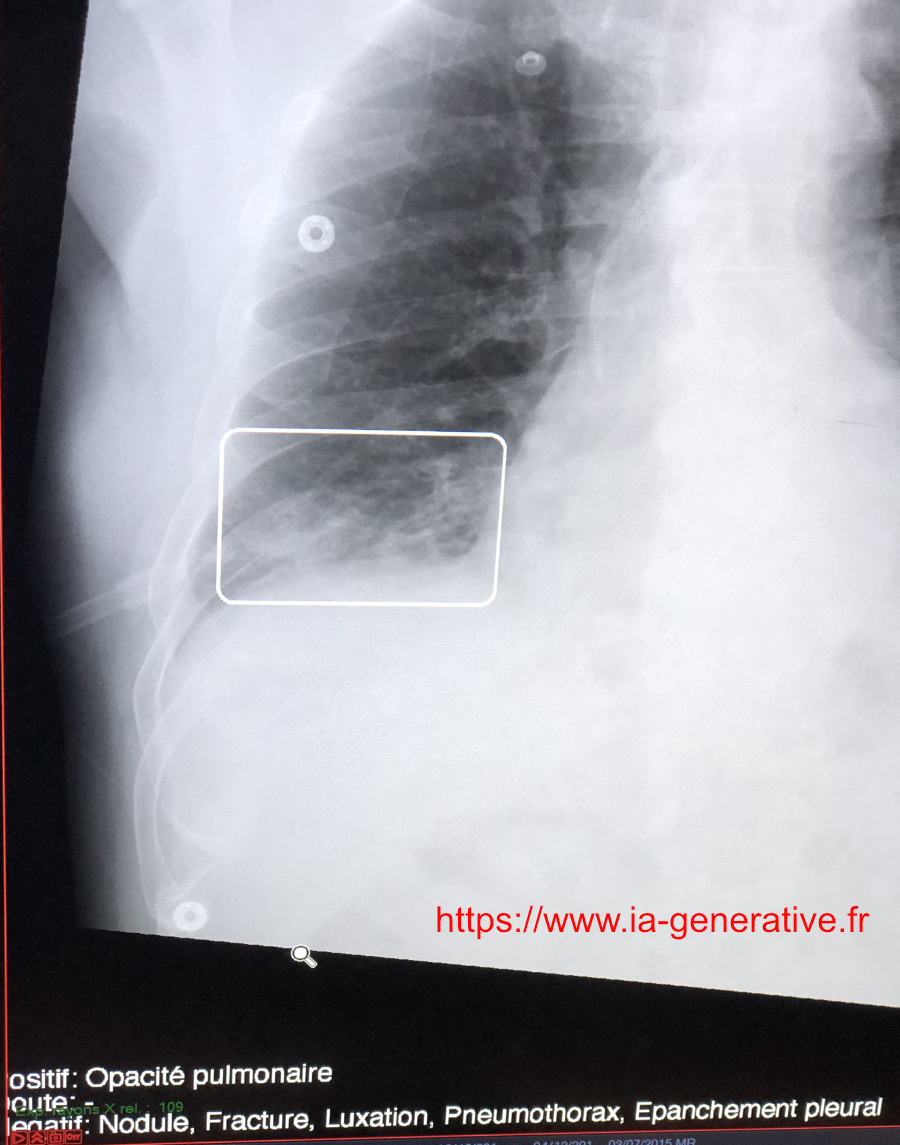

Il existe deux principaux logiciels d'IA en Radiologie: Milvue (Incepto) et Gleamer.

Ils étudient les radios conventionnelles, et détectent les fractures, les épanchements, etc.

Quand ils trouvent une anomalie qu'ils considèrent comme certaine, ils l'encadrent d'un rectangle blanc, comme ci-dessous (pneumopathie).